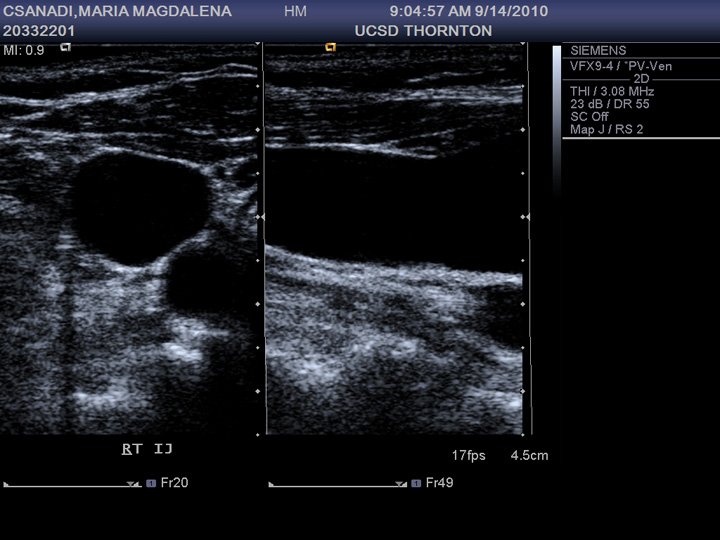

Residual clot on ultrasound Angiologist Do Blood Clots Show Up On Ultrasound There are also versions of these tests that look for specific types of blood clots: Tests used to diagnose or rule out dvt include: The first diagnostic method that is usually performed to image or see the clot is ultrasound—specifically, duplex ultrasound. “duplex” refers to the two parts of the process: While it's true signs and symptoms of dvt can. Do Blood Clots Show Up On Ultrasound.